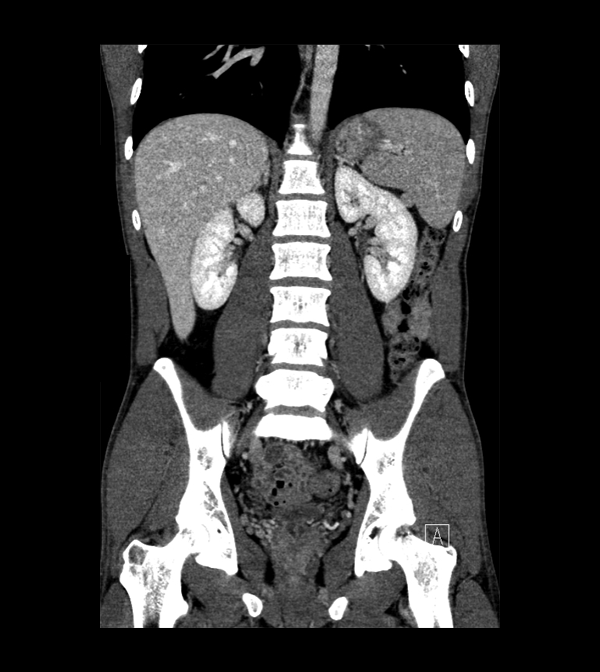

Body

Covers abdominal CT anatomy.